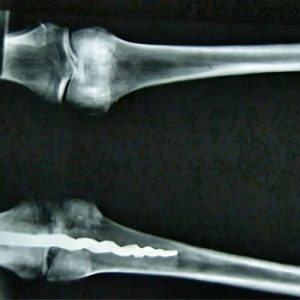

Una straordinaria scoperta è stata effettuata esaminando una mummia risalente ad oltre 3.000 anni fa. I ricercatori della UCLA’s Fielding School of Public Health avrebbero riscontrato una vite ortopedica metallica di 23 centimetri a livello del ginocchio di un soggetto di sesso maschile.

Il soggetto parrebbe essere deceduto in un periodo compreso tra il XVI e l’XI secolo avanti Cristo. La vite è stata “fissata” utilizzando una resina organica simile all’attuale cemento osseo. In questo modo è stato garantito un corretto mantenimento in posizione.

L’ipotesi dei ricercatori sarebbe proprio quella di un intervento chirurgico effettuato attorno all’XI secolo avanti Cristo sul ginocchio della persona. Tutti si sono dichiarati stupefatti analizzando la vite metallica presente, assolutamente sovrapponibile per forma e dimensione a quelle attuali più moderne, ma risalente a migliaia di anni fa.

“Il design utilizzato sarebbe lo stesso che oggigiorno permette la migliore stabilizzazione ossea”, spiega il dr. Richard Jackson, chirurgo ortopedico della Brigham Young University.

Il dr. Jackson ipotizzò che la persona potesse avere subito un’amputazione traumatica dell’arto inferiore. La rotula e la fibula infatti non sarebbero mai state rinvenute. L’evento probabilmente causò la morte dell’uomo e, in vista dell’inumazione, l’arto venne riattaccato utilizzando tale tecnica.